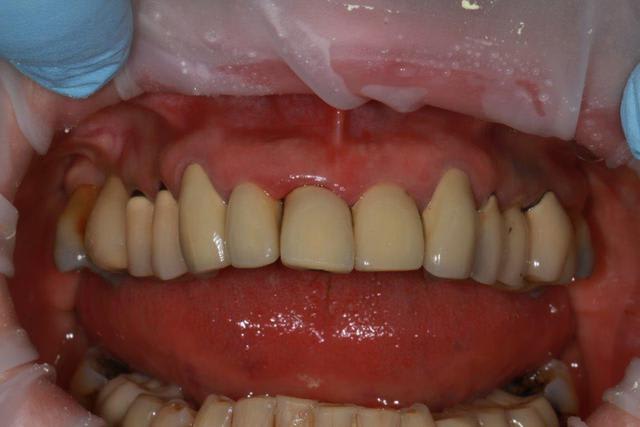

Rien qu en regardant la photo de face , je te dis oui :

L aspect de la gencives et la forme des dents suffit .

Même si les limites prophétiques étaient correctes , il y aurait ce style de gencives .